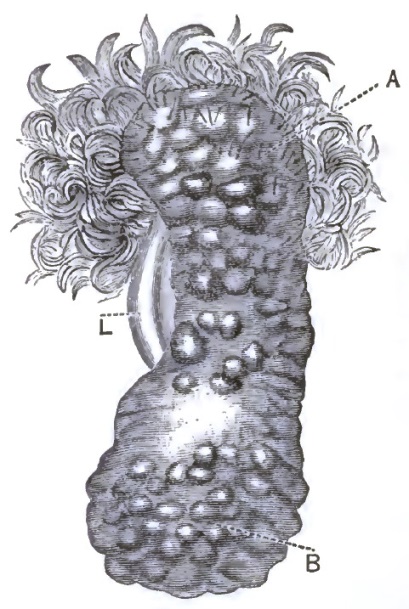

| 1. | THE CLASSICAL REPRESENTATION OF THE PELVIC ORGANS |

| 2. | THE CORRECT REPRESENTATION OF THE PELVIC ORGANS |

| 3. | FIRST DEGREE OF PROLAPSE OF THE POST-PARTUM UTERUS |

| 4. | SHOWING EXTREME DESCENT OF THE UTERUS AND OF THE PELVIC FLOOR, AND THE HERNIAL CHARACTER OF THE LESION |

| 5. | DESCENT OF THE VIRGIN UTERUS INTO THE VAGINAL CANAL, SHOWING THE REDUPLICATED VAGINAL WALLS |

| 6. | DESCENT OF THE UTERUS, SHOWING EXCESSIVE CIRCULAR ENLARGEMENT OF THE LACERATED CERVIX, CONSEQUENT UPON REDUPLICATION OF THE VAGINAL WALLS AND OUT-ROLLING OF INTRACERVICAL TISSUES |